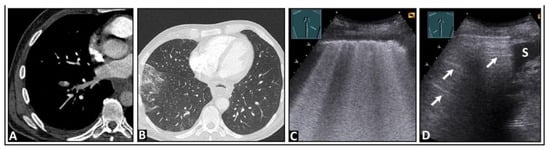

8. Pleural Artifacts with Simultaneous Presence of Consolidation